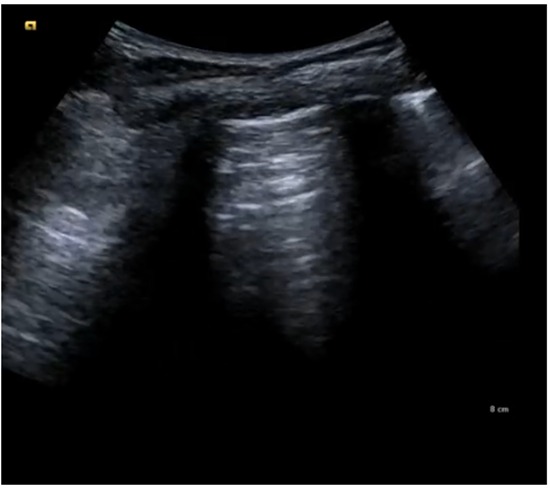

A la auscultación pulmonar destaca disminución de murmullo vesicular de campos derechos. Resto de exploración física por aparatos anodina.

Tras la realización de toracostomía con colocación de tubo pleural por neumotórax espontáneo, el paciente muestra evolución favorable. Se observa mejoría progresiva de la disnea y desaparición del dolor torácico.Los controles radiológicos posteriores confirman expansión pulmonar adecuada y reducción del neumotórax. Los signos vitales se mantienen estables, sin datos de compromiso hemodinámico. El paciente tolera la movilización y la oxigenoterapia de bajo flujo sin dificultad.

La realización de un examen físico detallado, complementado con radiografía de tórax, permite establecer un diagnóstico preciso de neumotórax en el contexto de la emergencia hospitalaria. El examen físico orienta al identificar signos clínicos como disminución de los ruidos respiratorios y desviación de estructuras en casos graves. La radiografía de tórax confirma la presencia de aire en el espacio pleural, el colapso pulmonar y la extensión del neumotórax, proporcionando información para decidir el manejo inmediato. La integración de ambos métodos diagnósticos asegura una evaluación rápida y confiable, fundamental en situaciones de urgencia.